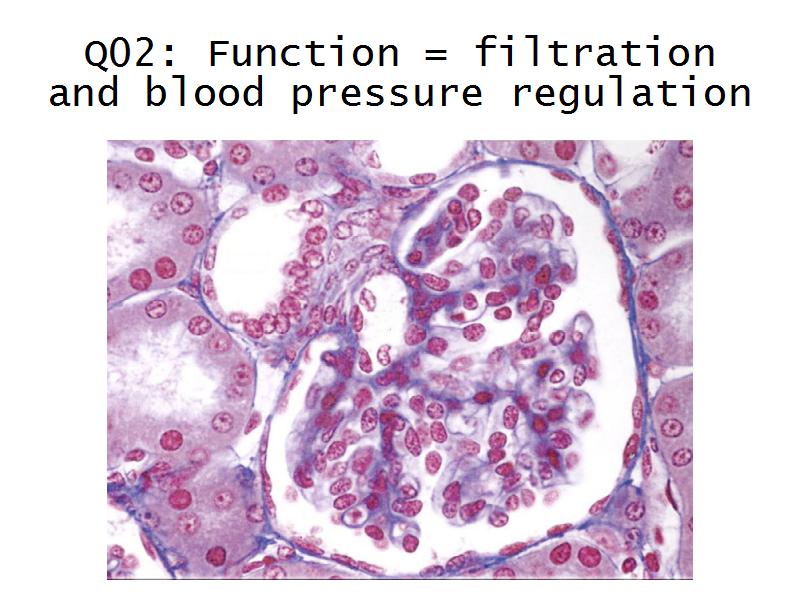

Kidney

Kidney

Slides 28 & 76

Kidney: Objectives

- Basic anatomy of the kidney

- Basic arrangement of nephrons and collecting tubules in the kidney

- Structure of the nephron and collecting tubules

- The renal corpuscle